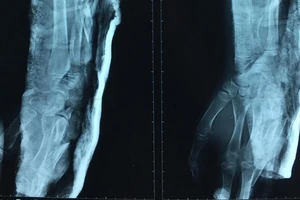

Cứu bệnh nhi bị chân vịt ghe chém gãy xương cánh tay